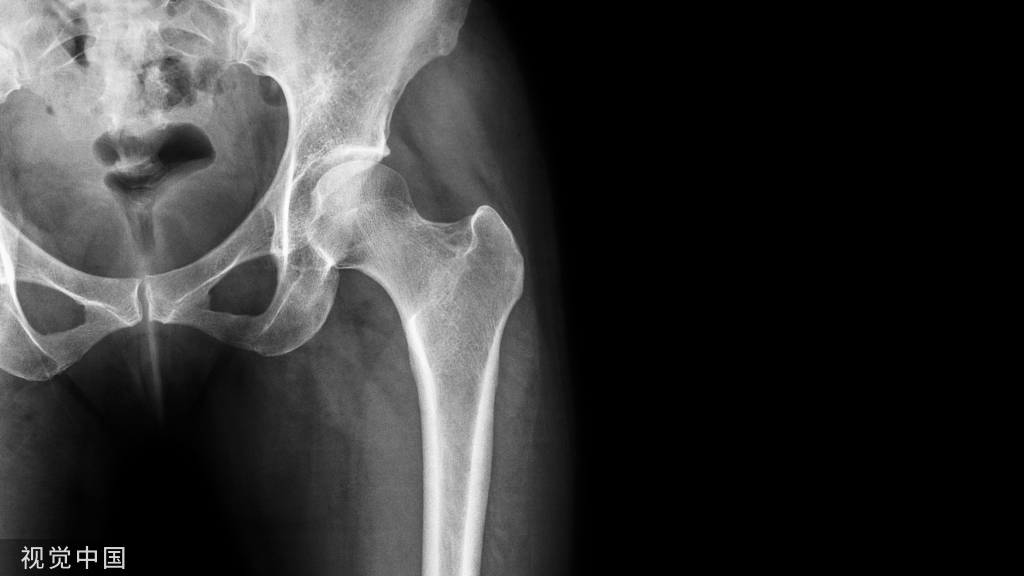

股骨假体前倾角(A)计算为假体股骨颈相对于上髁线的夹角(B)。